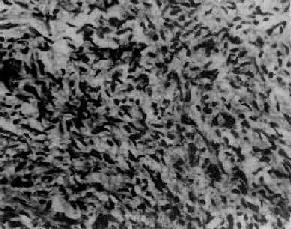

肉眼观,肿呈圆形、卵圆形或分叶状,大小不等,多数小于15cm,表面光滑,常有完整的包膜。切面多为实性,质地稍硬,肿呈黄白色,有些可呈囊性变,常有坏死出血区。多为单侧性。镜下,细胞多呈小圆形或多角形,胞浆少。核圆、椭圆或梭形,核膜清楚,核内常可见纵沟,核染色质细,可见1~2个核仁,核分裂像较少见。组织学类型有以下几种:分化较好的细胞常排列成小卵泡型(图13-20),呈菊形团或小腺泡状,中央为粉染蛋白液或退化的细胞核,称Call-Exner小体;有的排列呈大卵泡型、梁柱型或岛状等;分化较差的细胞常排列呈弥漫型或波纹状、脑回状或肉样构型。

图13-20 粒层细胞

细胞排列成小卵泡型,部分细胞核呈现核沟